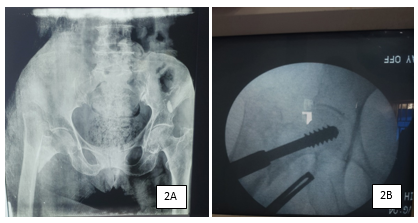

This is a retrospective study of 121 adult patients who had DHS screw fixations on account of proximal femoral fractures within 3 years period (from June 2015 to May 2018). The study site was Orthopaedic Hospital Wamakko, located in Sokoto, North-western region of Nigeria. Formal ethical approval with Ref no. SMH/1580/V.IV was obtained from the Ministry of Health, Sokoto, Nigeria before embarking on the study. Patients’ records were retrieved and data was collected using a self-administered questionnaire and further information was collected during the outpatient clinic visits. The inclusion criterion was hip fractures (Cervical, Intertrochanteric and subtrochanteric) in adult patients with complete records and a minimum of 6 months follow-up. The exclusion criteria were fractures in children, open fractures, neglected fractures for more than 4 weeks, associated hip dislocation, and femoral head and acetabular fractures. There were initially 162 patients included in the study but due to incomplete records, 21 were excluded and 121 patients were included among the study subjects. The relevant demographic data, duration of fracture, injury mechanism, fracture position and type (Figure 1A & 2A), associated fractures and co-morbidities, the interval before surgery, and Parker mobility score were recorded. Descriptive statistics was employed to present our data and the outcomes of the study.

Figure 1 60 year old woman presented with 1 week history of fall, sustained right intertrochanteric fracture (1A). Intraoperative pictures showing inserted guide wire (1B), triple reaming (1C) and final DHS fixation (1D).

The patient was positioned supine on a traction table and was given either spinal or general anaesthesia. All patients had a single injection of prophylactic 3rd generation Cephalosporin 30 minutes before skin incision as per unit protocol. The fracture was first reduced using image intensification guidance, with the use of traction and slight internal rotation. The presence of smooth medial and anterior cortical bony buttressing on the image indicates satisfactory reduction. An attempt was made to avoid varus mal-alignment of the neck-shaft angle. For patients with late presentation or fracture that could not be reduced using the closed reduction method, the fracture was reduced after opening the fracture site through a lateral approach to the proximal thigh. When the bone was reached and exposed, a guide wire was inserted parallel to the neck after making a small drilled hole which was advanced until the required position and tip-apex distance were obtained (Figure 1B). The pathway of the guide wire was drilled using a DHS triple reamer which was adjusted to the rough length of the DHS screw to be used (Figure 1C). At this stage, tapping may not be necessary, especially in osteoporotic bones. The required screw length (usually 60-95mm) was mounted on the T handle and driven to the appropriate position in the femoral head with the use of intraoperative image guidance (Figure 1D & 2B). The 1350 (4 to 8 holes) DHS side plate was fixed to the screw and a minimum of 2 cortical screws were used to hold the plate in place. Following this, the longitudinal traction was released before the final locking of the locking screw which prevents proximal fragment rotation and further reduced the fracture gap for more stability. Stability was tested by a hip range of motion followed by layered wound closure. In cases of delayed presentation and failure to achieve closed reduction, the fracture site has to be open first to release any fibrous tissue and callus to achieve desirable fracture reduction. This may cause more bleeding and prolong operation time compared to cases with early presentation.